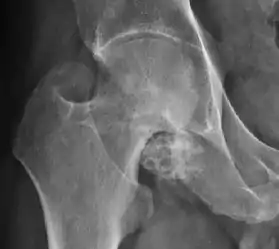

Synovial chondromatosis can be confidently diagnosed by X-ray when calcified cartilaginous chondromas are seen. However, other synovial proliferative processes, such as pigmented villonodular synovitis, require MRI for accurate diagnosis, although noncalcified synovitis can be suspected in radiographs by indirect signs, such as soft tissue swelling and/or erosions in the femoral head, femoral neck, or acetabulum (Figure 7).[1]

Figure 7:

Axial CT image of pigmented villonodular synovitis eroding the posterior cortex of the femoral neck.[1]

X-ray of synovial chondromatosis.[1]

CT of synovial chondromatosis.[1]

In synovial proliferative disorders, MRI demonstrates synovial hypertrophy. In the case of PVNS, characteristic foci of low signal intensity related to hemosiderin deposition are better seen on gradient echo T2* images (Figure 7). In the case of synovial osteochondromatosis, the synovial hypertrophy is accompanied by intermediate signal cartilaginous loose bodies and/or low signal calcified loose bodies.[1]